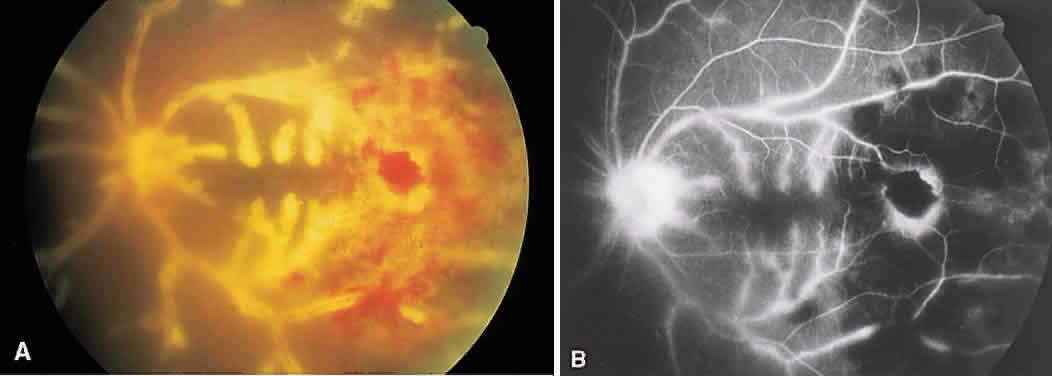

SARCOIDOSIS

Sarcoidosis is a systemic, idiopathic, noncaseating, granulomatous disease that affects various organs, including the eye, brain, lung, and skin. Ocular findings may include conjunctival nodules; anterior iridocyclitis; vitreous cells; retinal, optic nerve, and choroidal granulomas (Fig. 7A); retinal vasculitis (venules are preferentially affected); cystoid macular edema; retinal vessel occlusion; and disc and retinal neovascularization.

Fig. 7. Sarcoidosis. A. Choroidal granuloma. B. Fluorescein angiogram shows staining of the choroidal granuloma.

The FA reflects the various clinical entities. Retinal venular walls stain, particularly where there are perivenular exudates.25–27 More extensive venous involvement can produce a picture of dilated veins and perivenous leakage.27 Peripheral neovascularization occurs near areas of retinal capillary nonperfusion.25,28 Optic disc granulomas and optic disc neovascularization both leak extensively (Fig. 8A); sarcoid retinal lesions also stain (see Fig. 7B).27 In disc edema, the disc is hyperfluorescent and leaks fluorescein (see Fig. 8B).25

Fig. 8. Sarcoidosis. A. Fluorescein angiography shows two separate areas of neovascularization of the peripheral retina. B. Extreme leakage of dye from the right disc with cystoid macular edema of the right macular region in a patient with chronic sarcoidosis.

Four main patterns can be identified with ICG angiography. The first and most common pattern is hypofluorescent dark spots in the early and intermediate phases of the angiogram. These spots either become isofluorescent or remain hypofluorescent in the late phases. The second pattern is focal hyperfluorescent spots seen in the intermediate and late phases. The third pattern is fuzzy choroidal vessels due to perivascular choroidal leakage in the intermediate phase. Finally, the fourth pattern is characterized by diffuse zonal hyperfluorescence representing choroidal staining in the late phase of the angiogram. The latter two patterns resolved after systemic corticosteroid treatment.29